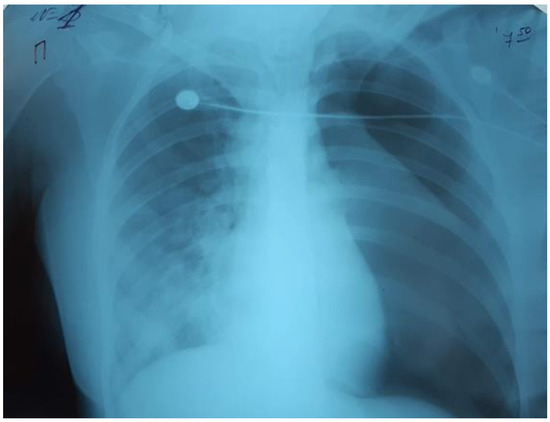

Successful Use of Ecmo in the Treatment of Acute Respiratory Distress Syndrome Associated with Sars-Cov-2 in Two Pediatric Cases

by Mariia Stasiv, Volodymyr Mishchuk, Natella Basa and Halyna Lytvyn

SARS-CoV-2 infection, in the vast majority, affects adult patients. The severity of COVID-19 and mortality are directly correlated with the increasing age of patients and the number of comorbidities. However, with the further development of the COVID-19 pandemic, severe cases of COVID-19 have been reported in children. About 0.8–1% of sick children require hospitalization in an intensive care unit. The main syndromes that cause disease severity and mortality in children are acute respiratory distress syndrome, multisystem inflammation syndrome and multiple organ failure. The rapid development of severe respiratory failure and hypoxemia in respiratory distress syndrome leads to the use of various methods of respiratory therapy, and in case of their ineffectiveness to extracorporeal membrane oxygenation (ECMO). In our report, we present two clinical cases of successful use of ECMO in children with COVID-19, who developed severe ARDS. Full article

Show Figures